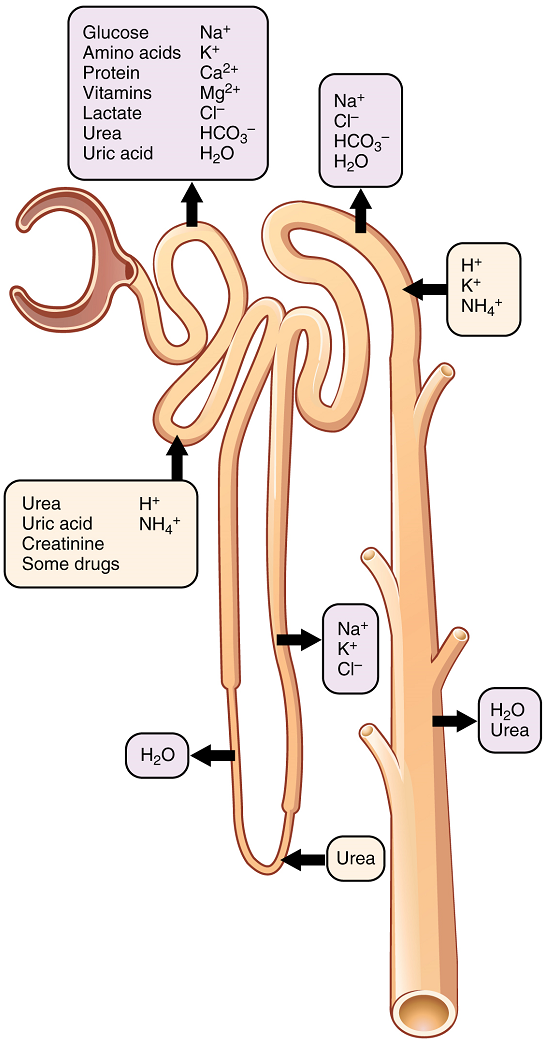

Reabsorption and Secretion in the Proximal Convoluted Tubule

The first point at which the forming urine is modified is in the proximal convoluted tubule. Here, some substances are reabsorbed, whereas others are secreted. Note the use of the term “reabsorbed.” All of these substances were “absorbed” in the digestive tract—99 percent of the water and most of the solutes filtered by the nephron must be reabsorbed. Water and substances that are reabsorbed are returned to the circulation by the peritubular and vasa recta capillaries (Figure 7). Movement of water into the peritubular capillaries and vasa recta will be influenced primarily by osmolarity and concentration gradients. Sodium is actively pumped out of the proximal convoluted tubule into the interstitial spaces between cells and diffuses down its concentration gradient into the peritubular capillaries. As it does so, water will follow passively to maintain an isotonic fluid environment inside the capillary. Most of that fluid and its contents are reabsorbed. That recovery occurs in the proximal convoluted tubule, loop of Henle, distal convoluted tubule, and the collecting ducts (Table 1 and Figure 9). Various portions of the nephron differ in their capacity to reabsorb water and specific solutes. While much of the reabsorption and secretion occur passively based on concentration gradients, the amount of water that is reabsorbed or lost is tightly regulated. This control is exerted directly by antidiuretic hormone and another hormone aldosterone. Most water is recovered in the proximal convoluted tubule, loop of Henle, and distal convoluted tubule. About 10 percent (about 18 L) reaches the collecting ducts. The collecting ducts, under the influence of antidiuretic hormone, can recover almost all of the water passing through them.

Most of the Ca2+, Na+, glucose, and amino acids must be reabsorbed by the nephron to maintain homeostatic plasma concentrations. Other substances, such as urea, K+, ammonia (NH3), creatinine, and some drugs are secreted into the filtrate as waste products. Acid–base balance is maintained through actions of the lungs and kidneys. In the case of urea, about 50 percent is passively reabsorbed by the proximal convoluted tubule.

A few of the substances that are transported with Na+ include Cl–, Ca2+, amino acids, glucose, and PO43−. Sodium is actively exchanged for K+ using ATP on the basal membrane.

About 67 percent of the water, Na+, and K+ entering the nephron is reabsorbed in the proximal convoluted tubule and returned to the circulation. Almost 100 percent of glucose, amino acids, and other organic substances such as vitamins are normally recovered here.

More substances move across the membranes of the proximal convoluted tubule than any other portion of the nephron.

Reabsorption and Secretion in the Loop of Henle

The descending and ascending portions of the loop are highly specialized to enable recovery of much of the Na+ and water that were filtered by the glomerulus. As the forming urine moves through the loop, the osmolarity will change from isosmotic with blood to both a very hypertonic solution and a very hypotonic solution. These changes are accomplished by osmosis in the descending limb and active transport in the ascending limb. Solutes and water recovered from these loops are returned to the circulation by way of the vasa recta.

Descending Loop: The majority of the descending loop is comprised of simple squamous epithelial cells; to simplify the function of the loop, this discussion focuses on these cells. These membranes have permanent aquaporin channel proteins that allow unrestricted movement of water from the descending loop into the surrounding interstitial fluid. Approximately 15 percent of the water and modest amounts of urea, Na+, and other ions are recovered here.

Most of the solutes that were filtered in the glomerulus have now been recovered along with a majority of water, about 82 percent. As the forming urine enters the ascending loop, major adjustments will be made to the concentration of solutes to create urine.

Ascending Loop: The thick portion is lined with simple cuboidal epithelium It is completely impermeable to water due to the absence of aquaporin proteins, but ions, mainly Na+, are actively pumped out of the loop by large numbers of the Na+/K+ ATPase pump (active transport). This causes the removal of Na+ while retaining water leading to a hypotonic filtrate by the time it reaches the distal convoluted tubule.

The Na+/K+ ATPase pumps allow Na+ to be actively pumped into the interstitial fluid, Cl– follows the Na+ from the lumen into the interstitial fluid.

In addition, collecting ducts have urea pumps that actively pump urea into the interstitial spaces. This results in the recovery of Na+ to the circulation via the vasa recta and creates a high osmolar environment in the depths of the medulla.

At the same time that water is freely diffusing out of the descending loop through aquaporin channels into the interstitial spaces of the medulla, urea freely diffuses into the lumen of the descending loop as it descends deeper into the medulla, much of it to be reabsorbed from the forming urine when it reaches the collecting duct. Thus, the movement of Na+ and urea into the interstitial spaces by these mechanisms creates the hyperosmotic environment of the medulla. The net result of this is to recover both water from the descending limb of the loop of Henle and Na+ in the circulation (Figure 10).

Reabsorption and Secretion in the Distal Convoluted Tubule

Approximately 80 percent of filtered water has been recovered by the time the dilute forming urine enters the distal convoluted tubule. The distal convoluted tubule will recover another 10–15 percent before the forming urine enters the collecting ducts. Aldosterone increases the amount of Na+/K+ ATPase in the basal membrane of the distal convoluted tubule and collecting duct. The movement of Na+ out of the lumen of the collecting duct creates a negative charge that promotes the movement of Cl– out of the lumen into the interstitial space. Peritubular capillaries receive the solutes and water, returning them to the circulation.

Cells of the distal convoluted tubule also recover Ca2+ from the filtrate. Parathyroid hormone stimulates the insertion of Ca2+ channels in the luminal surface of DCT cells. Any Ca2+ not reabsorbed at this point is lost in the urine.